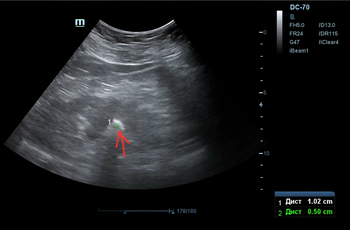

Делаем УЗИ почек (фото 3 — 5) — по центру левой почки подозрение на твёрдый камень, будто состоящий ~ из трёх слившихся фрагментов.

Фото 4 — УЗИ почки